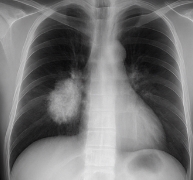

- 흉부 X-ray 검사: 폐 구조 확인.

- 저선량 CT 검사: 조기 폐암 진단에 효과적.